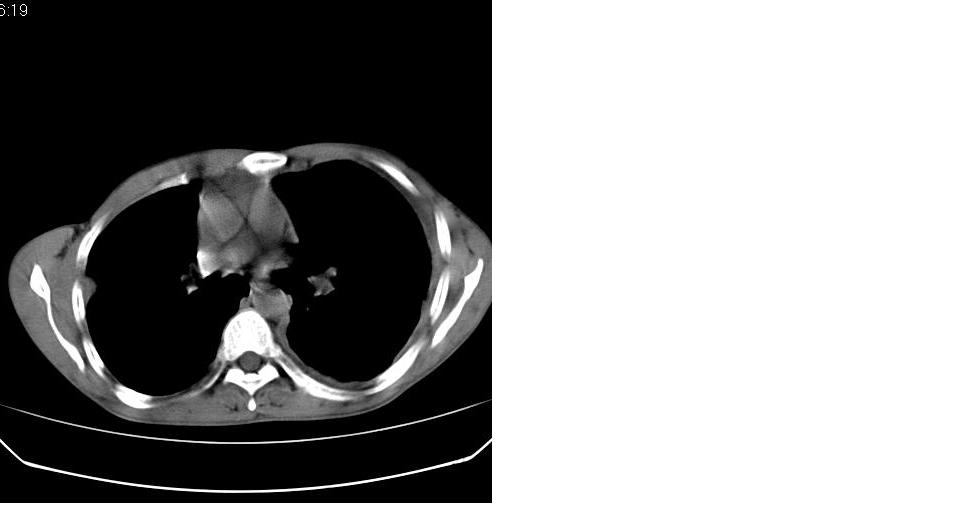

以下是引用苯小孩在2007-6-27 15:09:00的发言:[br]考虑:1、右肺继发性肺结核.2、双侧包裹性积液<胸腔及叶间>3、双侧局部胸膜增厚.[br]建议胸水化验检查.

以下是引用yanghaochen88在2007-6-27 15:08:00的发言:[br]双肺上野散在粟粒状影、包裹性积液、胸膜增厚粘连、叶间积液---tb,至于分型还得结合病史体征细究妥当些。

以下是引用zjzjr在2007-6-27 16:49:00的发言:[br]肺结核、结核性胸膜炎。